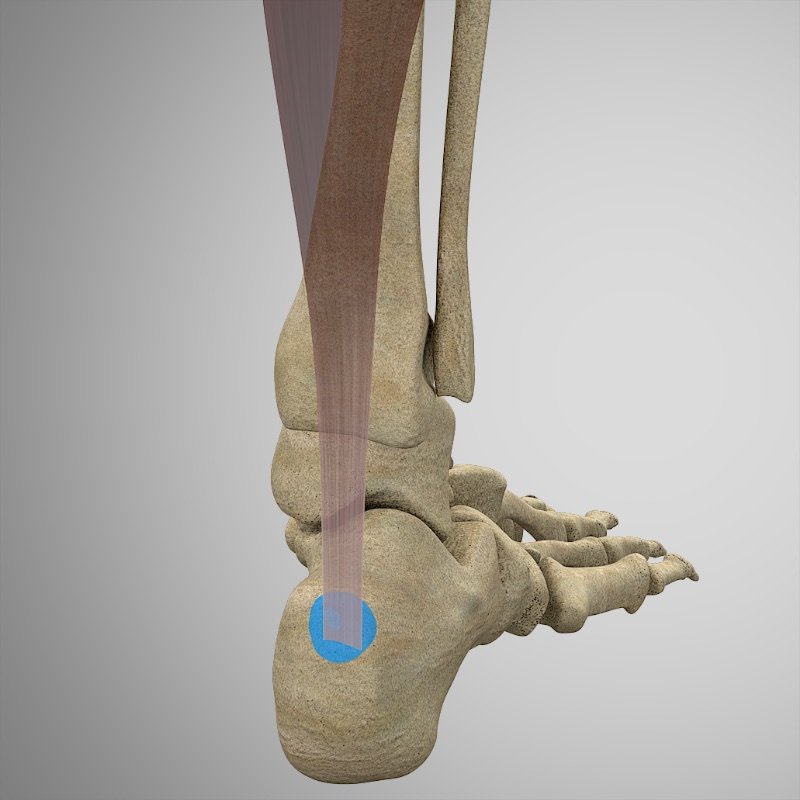

INSERCIÓN

- Calcáneo a través del tendón de Aquiles